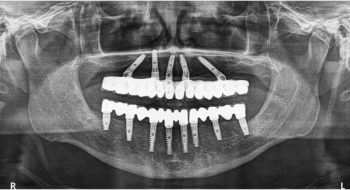

Tooth implant procedure (Dental implant procedure)?

Tooth implant surgery is a procedure that replaces missing tooth or damaged tooth with screw like bio-compatible material called titanium or zirconium. The damaged tooth is removed and the tooth implant is placed in the jaw bone under anaesthesia by an implantologist. Once the tooth implant is placed in the jaw bone, it is allowed to heal and osseointegrate (fuse with the surrounding bone) to become part of the human body. After 4-6 months’ time, the crown is placed on the implant to restore the functionality of the tooth.